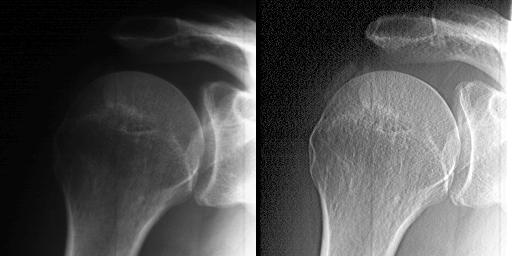

Local adaptation of contrast and binning of pixels. Calcifying supraspinatus tendinitis in the context of a shoulder periarthritis. (Medical informations related to this picture: DrABiz). Radiographic material kindly loaned by Sion Hospital and scanned at Geneva Observatory. Grace to the binning, the pixels issued by the 8-bits scanner are transformed to ~12-bits metapixels.